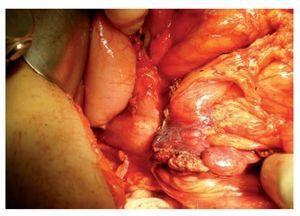

Se trata de un hombre de 54 años con antecedente de cáncer de colon en tres tíos maternos, cuatro primos y tres sobrinos, así como cáncer de páncreas en dos sobrinos. Todos ellos fueron diagnosticados entre los 35 y 55 años. El paciente tenía historia de hemorragia del tubo digestivo bajo de un mes de evolución. También presentaba dolor abdominal en mesogastrio tipo cólico e intermitente. A la exploración física se encontró hiperbaralgesia en el mesogastrio y dentro de sus exámenes de laboratorio presentó anemia ferropénica. Se le realizó una esófagogastroduodenoscopia y una colonoscopia que detectaron gastropatía no erosiva y una lesión de aspecto neoplásico en ángulo hepático del colon con patrón infiltrante y una zona de estrechez. Las biopsias de la mucosa obtenida de ese sitio demostraron un adenocarcinoma. Mediante una tomografía se observó un tumor colónico ulcerado en el ángulo hepático de 10 cm en su eje mayor con invasión al duodeno (Figura 1). El paciente recibió nutrición parenteral preoperatoria por una semana. El valor del antígeno carcinoembrionario fue de 17 mcg/L. En la laparotomía exploradora se demostró invasión del tumor al duodeno y al páncreas (Figura 2). Se le realizó una pancreatoduodenectomía clásica y hemicolectomía derecha en bloque, con resección lateral de la vena mesentérica superior (Figura 3). El estudio histopatológico definitivo demostró un carcinoma poco diferenciado con aspecto medular de colon derecho que invadió duodeno, páncreas y estómago, pero con bordes y ganglios linfáticos negativos, de entre 31 que se analizaron, por lo que se calificó como T4N0M0 (Figura 4). Se realizó estudio inmunohistoquímico de MSH-6 y MLH-1, en los que se demostró presencia de marca nuclear en la mucosa residual y en las células epiteliales neoplásicas, resultados sugerentes de estabilidad de las enzimas de reparación del ácido desoxirribonucleico (DNA) estudiadas. En el periodo posoperatorio, el paciente desarrolló una fístula pancreática y un cúmulo intraabdominal secundario; la fístula se trató con una punción guiada por tomografía, antibióticos y nutrición parenteral.

Figura 3. Fotografía del campo quirúrgico en la que se observa la antrectomía, pancreatectomía, resección del duodeno a la altura del ángulo de Treitz y un punto de sutura sobre la resección en cuña de la vena mesentérica superior.